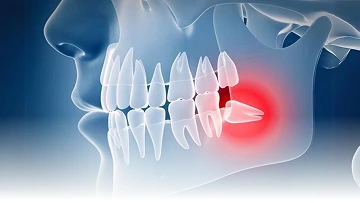

Gigi bungsu adalah gigi geraham ketiga yang biasanya tumbuh pada usia dewasa (18 Tahun keatas). Pertumbuhannya sering kali tidak sempurna karena keterbatasan ruang di rahang, sehingga dapat menyebabkan nyeri, peradangan, dan infeksi. Dalam kondisi tertentu, gigi bungsu perlu dilakukan tindakan pencabutan untuk mencegah masalah kesehatan gigi dan mulut.

Sayangnya, tidak semua orang mengalami pertumbuhan gigi bungsu yang normal. Gigi bungsu juga terkadang tumbuh hanya sebagian, miring ke depan atau ke belakang, melintang, atau tersangkut dengan gigi lainnya. Gigi bungsu yang tumbuh tidak normal ini disebut dengan impaksi (tertanam didalam gusi) gigi.

Saat impaksi gigi bungsu terjadi, kamu mungkin akan disarankan untuk menjalani operasi gigi bungsu. Meski begitu, tidak semua kasus impaksi gigi bungsu harus langsung dioperasi.

Ada beberapa gejala yang dapat menandyakan bahwa gigi bungsu mengalami infeksi atau masalah kesehatan lainnya, antara lain gusi bengkak, bau mulut, sakit gigi, dan pada kasus tertentu adalah keluarnya nanah dari gusi atau gigi bungsu yang bermasalah.